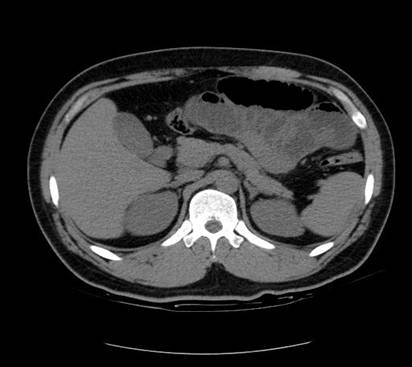

以下是引用zsl6918在2007-6-22 21:08:00的发言:[br]病史较长,反复发作,基本排除恶性病变,腹部定位像可见是小肠梗阻征象,原因无非是肠源性,血管性和神经性的,肠源性的在排除占位后应想到 肠旋转不良的可能,血管性的应想到肠系膜血管的栓塞,神经性的要想到植物神经功能紊乱的可能,本病例应该强化检查帮助诊断,个人感觉旋转不良可能性大。

以下是引用青莲居士在2007-6-24 12:27:00的发言:[br]肠梗阻[br]肝内胆管结石